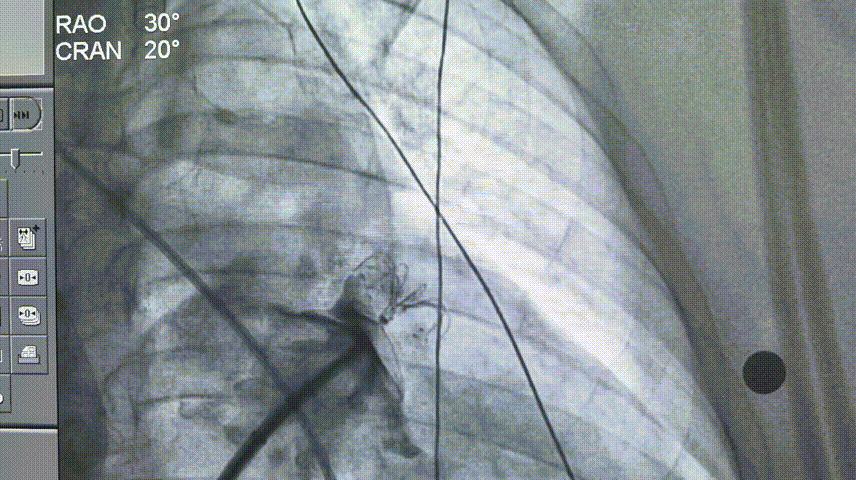

RAO 30° CAUD 20°测量锚定区:20.3mm;封堵区:24.0mm。

RAO 30° CAUD 20°造影

选择LAMax LAAC® 2430 Normal型号左心耳封堵器。

锚定伞锚定在主干区域,再将封堵盘逐渐打开,保证封堵效果,封堵盘完全打开后造影,外盘覆盖外口,封堵完全,无残余分流。

打开封堵盘

打开封堵盘造影